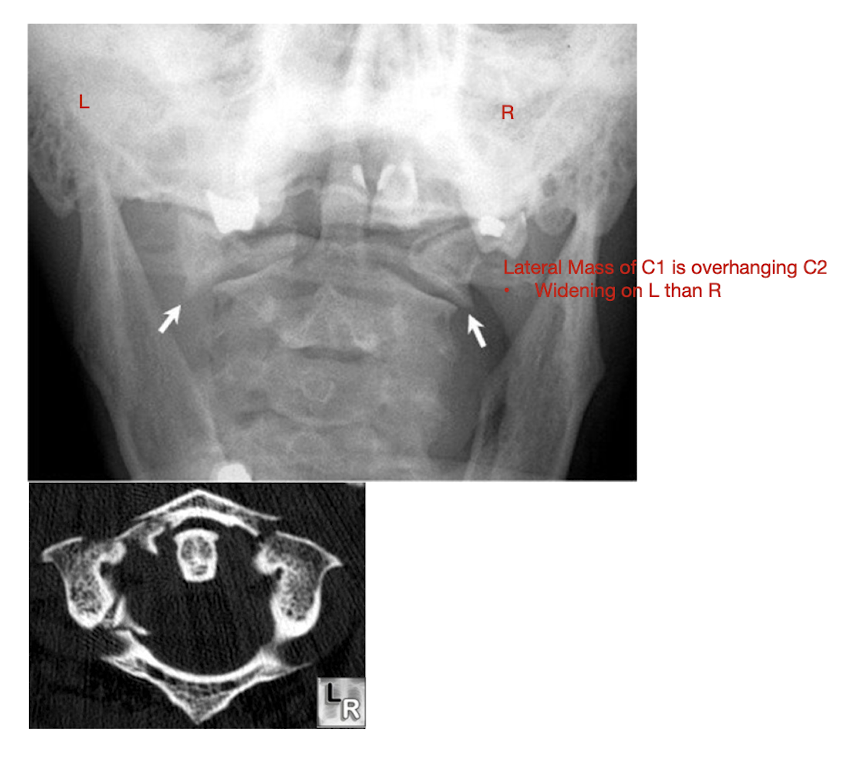

Fracture of C1: Jefferson Fx

Fracture of C1: Jefferson Fx

Rarely causes ___ injury

What direction of neck movement can cause head to slide forwards and compress SC?

Requires what type of view to diagnose?

Note displacement of what structure?

Neurological Injury

Fwd flex w Jefferson Fx

Open mouth view

Lateral Mass Displacement